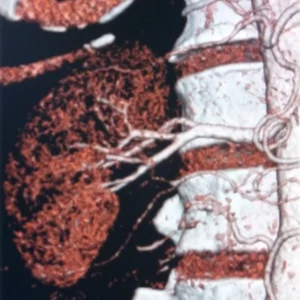

The kidneys are a pair of bean-shaped organs on either side of your spine, below your ribs and behind your belly. Each kidney is about 4 or 5 inches long, roughly the size of a large fist.

The kidneys’ job is to filter your blood. They remove wastes, control the body’s fluid balance, and keep the right levels of electrolytes. All of the blood in your body passes through them several times a day. Blood comes into the kidney, waste gets removed, and salt, water, and minerals are adjusted, if needed. The filtered blood goes back into the body. Waste gets turned into urine, which collects in the kidney’s pelvis — a funnel-shaped structure that drains down a tube called the ureter to the bladder.Each kidney has around a million tiny filters called nephrons. You could have only 10% of your kidneys working, and you may not notice any symptoms or problems. If blood stops flowing into a kidney, part or all of it could die. That can lead to kidney failure.